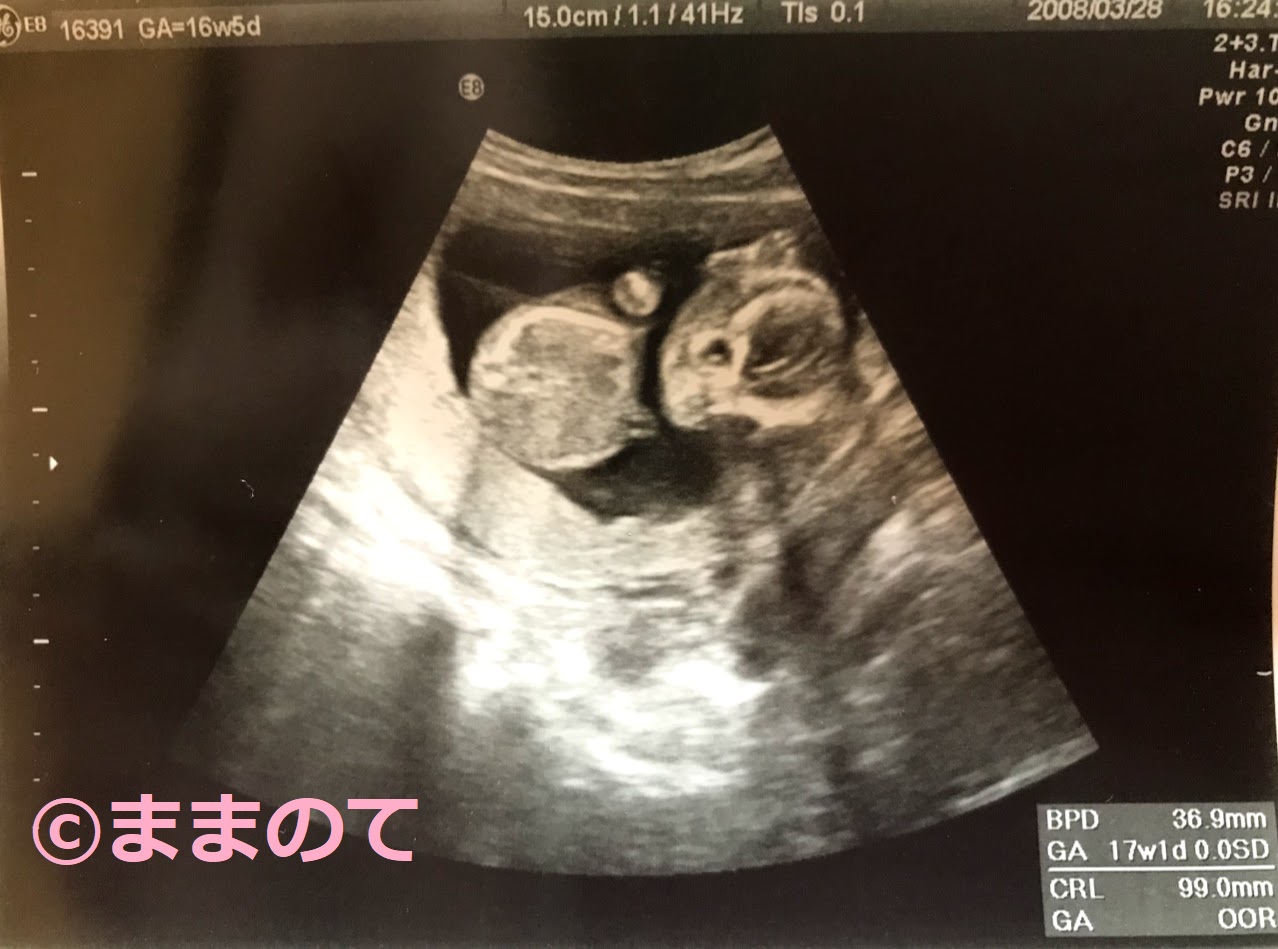

妊娠16週の赤ちゃんのエコー画像

妊娠16週5日の胎児を写したエコー写真です。BPDは36.9mm、CRLは99mm、身長は15cmと推定されています。バンザイをするように上げた手は頭の上まで届きそうです。小さな5本の指も、はっきりと見えていますね。顔やお腹がふっくらとしてきている様子が、エコーでもわかります。